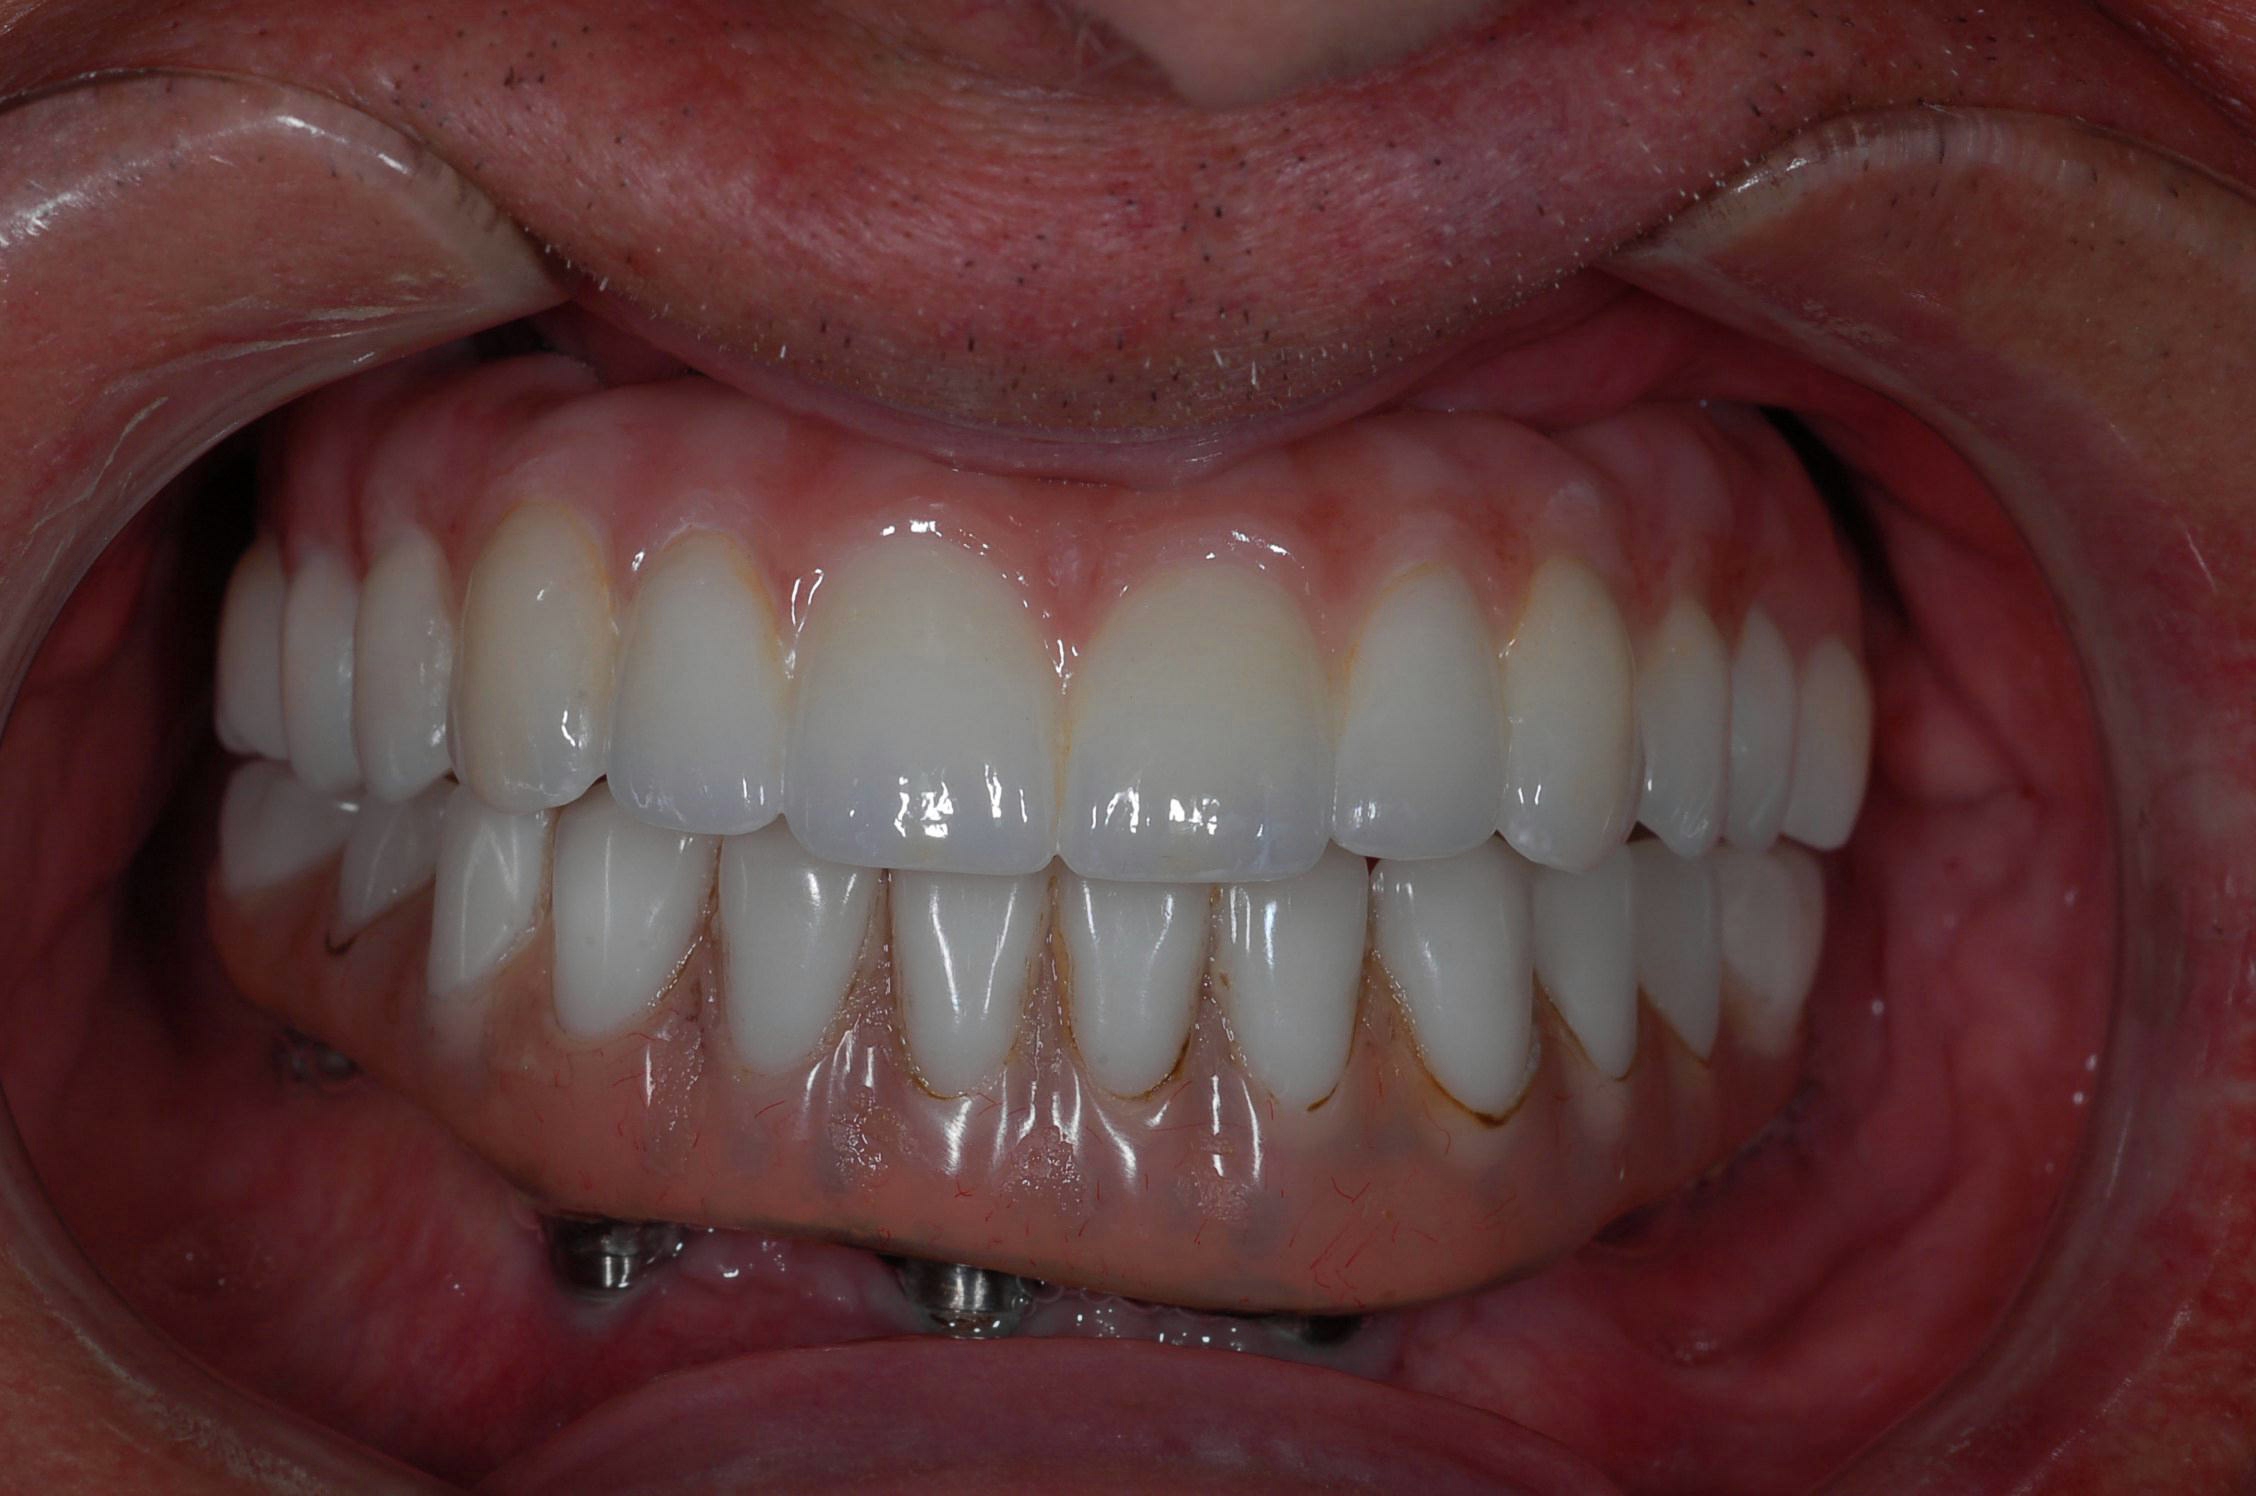

Fig 9. An implant retained over-denture was upgraded to a fixed zirconia hybrid.

Figure 9